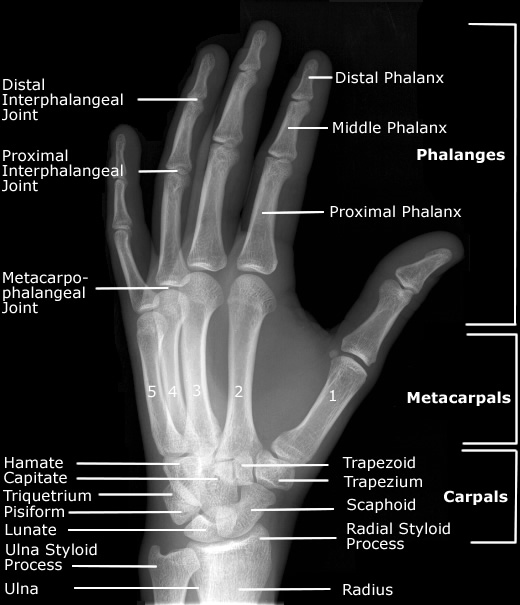

Berikut anatomi dari manus, bisa kita review sejenak, untuk menegtahui masing masing bagian dari manus.